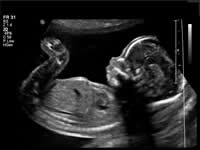

During pregnancy, ultrasounds are used to produce an image of the fetus. According to the American Pregnancy Association, there are seven types of ultrasounds: transvaginal, standard (2 dimensional or 2D), advanced (targeting a specific issue of concern), fetal echocardiography (assessing the heart), Doppler, 3D and 4D (also known as “dynamic” 3D because it focuses on the face and fetal movements). Ultrasounds are usually done in order to keep track of the pregnancy and to ensure that the baby is safe and healthy. 3D Ultrasound and 4D Ultrasounds have gained a lot of popularity with expecting parents.

Image Courtesy: upmc.com